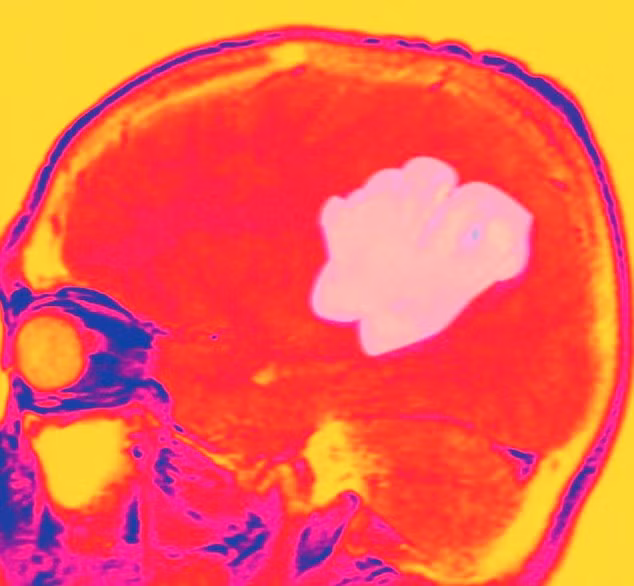

![]() |

| U não nguyên phát. |